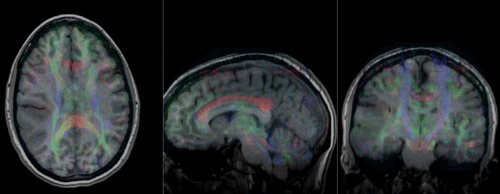

Slicer Registration Library Case #27: Intra-subject Brain DTI

This is a classic case of a multi-sequence MRI exam we wish to spatially align to the anatomical reference scan (T1-SPGR). The scan of interest is the DTI image to be aligned for surgical planning/reference.

• The DWI sequence (EPI) contains distortions we seek to correct via non-rigid alignment

• the DTI baseline is similar in contrast to a T2, albeit at much lower resolution

• we do not have a T2 weighted anatomical scan, but instead a T1 and a FLAIR. We use the FLAIR as the fixed image, because its contrast matches the DTI-baseline better than the T1, esp. in terms of tumor contrast.

Registered DTI superimposed on SPGR and T2 original and registered pair of T1 and DTI (animated gif, may have to be opened to animate)